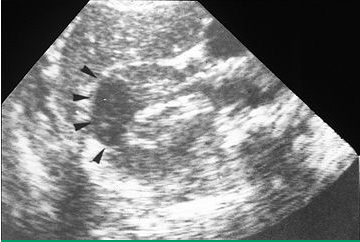

узи почек, ультразвуковое исследование почек, пиелонефрит, пиелонефрит на узи почек

Ультразвуковое исследование почек (УЗИ почек) позволяет увидеть лишь косвенные признаки воспаления чашечно-лоханочной системы почек (утолщение стенок), затруднение оттока мочи, анатомические особенности (рефлюкс) или грубую анатомическую патологию (стеноз мочеточников), абсцессы, камни в почках и т.д. Подробнее о симптомах, диагностике и лечении пиелонефрита.